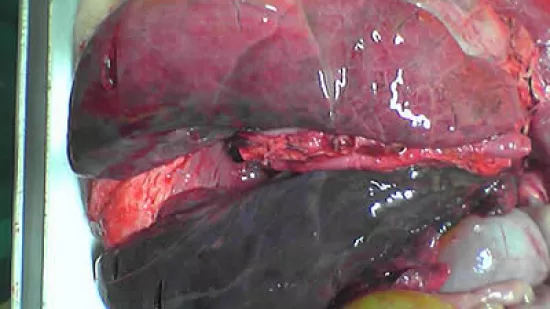

Quelle lésion peut être observée sur l’image ?